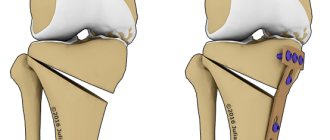

Разновидность

Сама пластинка бывает нескольких видов. Это та, что выполняет защитную функцию, (нейтрализационную), опорную (поддерживающую), компрессионную и при стяжении переломанных костей. Четыре вида в классификационном разделе.

Металлоостеосинтез – это предписание наложить на кость титановые пластины.